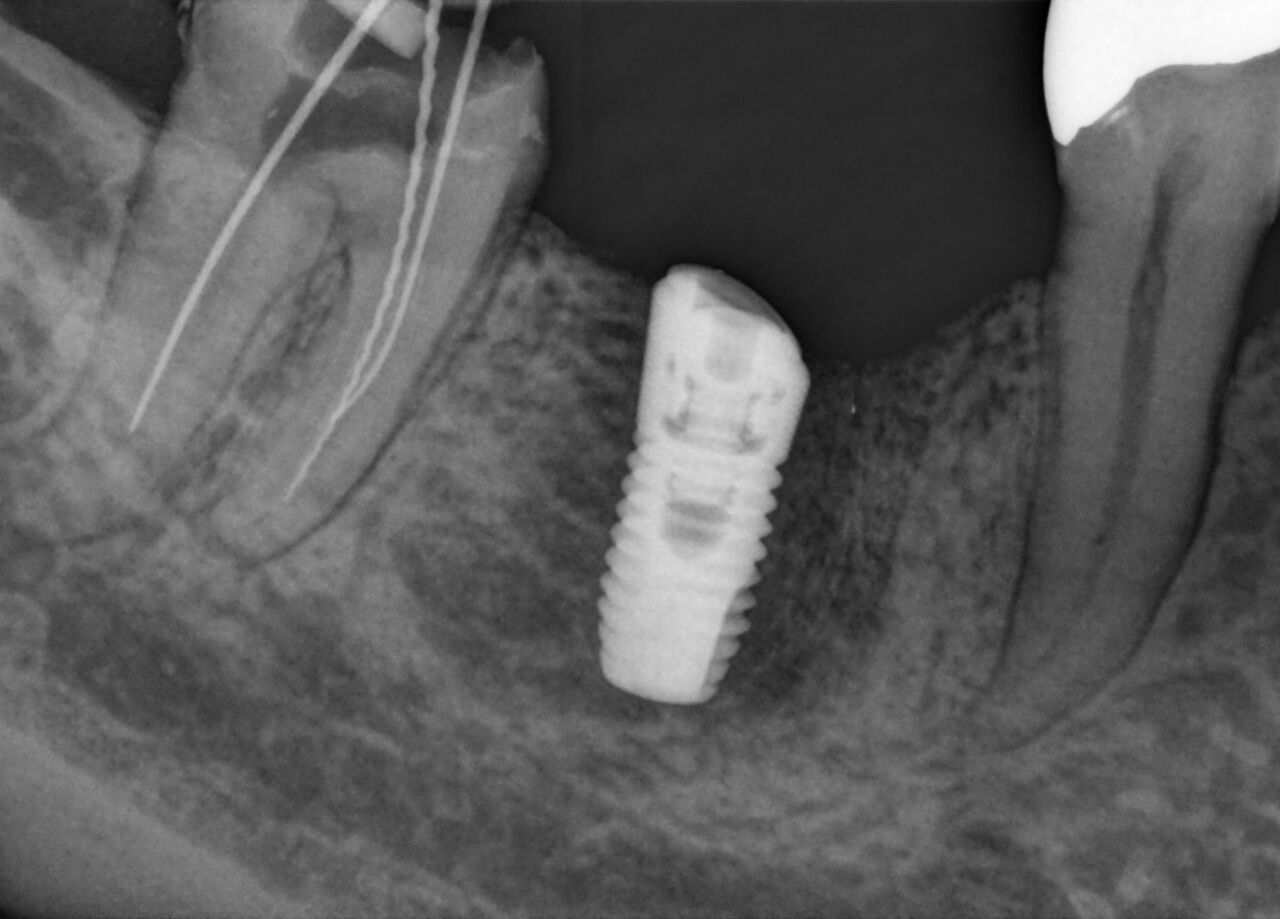

Schick AE sensors support a high clinical performance level with superior image quality and advanced filtering enhancements to highlight relevant anatomical structures and facilitate an accurate and detailed diagnosis. Low-noise images, improved visibility of details and dedicated filtering in indications such as endodontic cases or tooth decay, provide a relevant advantage in diagnostic certainty and help aid true confidence in the treatment assessment. When combined with smart connectivity between the hardware and Sidexis 4 software, you get the perfect partner for any practice.

Schick AE has a theoretical resolution of 33 lp/mm and a 15 μm pixel size. In combination with dedicated filters and the enhanced dynamic range you get superior X-rays to support your diagnosis.

Increased sensor sensitivity and an enhanced low-dose optimized exposure spectrum allow for optimal visibility and diagnostics at reduced exposure. Underexposed images are successfully counterbalanced, granting consistent image quality and dose flexibility.

"I have used an array of sensors over the years, but with the new AE sensor from Dentsply Sirona, I saw an immediate improvement in my image quality. With the advanced filtering enhancements and optimizations, I am confident that I am seeing all of the clinical details needed to support an accurate diagnosis."

Dr. Douglas Schultz, Kansas, USA